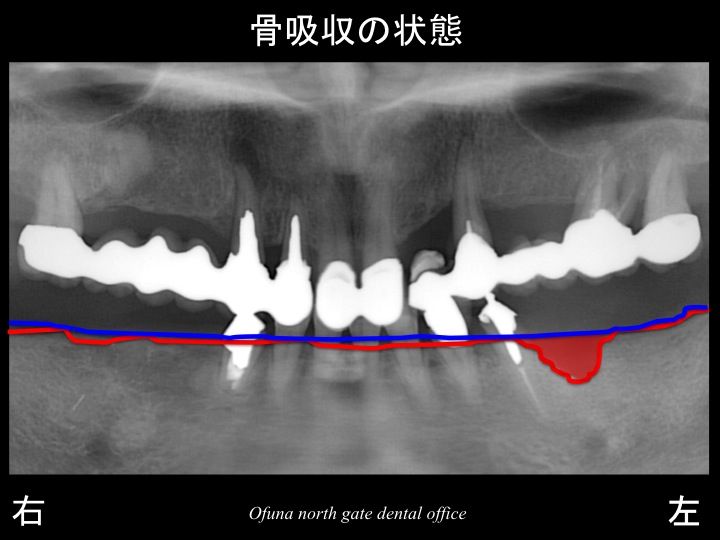

さらに わかりやすくするために、

骨吸収部位を赤色で表示します。

さらに骨吸収が大きいのが分かるかと思います。